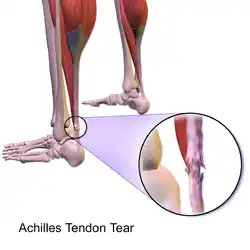

Anatomy

The Achilles tendon is the strongest and thickest tendon in the body.[13] It connects the calf muscles to the heel bone of the foot. The calf muscles are the gastrocnemius, soleus and the heel bone is called the calcaneus. It is approximately 15 centimeters (5.9 inches) long and begins near the middle part of the calf. Contraction of the calf muscles flexes the foot down. This is important in activities such as walking, jumping, and running. The Achilles tendon receives its blood supply from its muscular and tendon junction. Its nerve supply is from the sural nerve and to a lesser degree from the tibial nerve.[13]